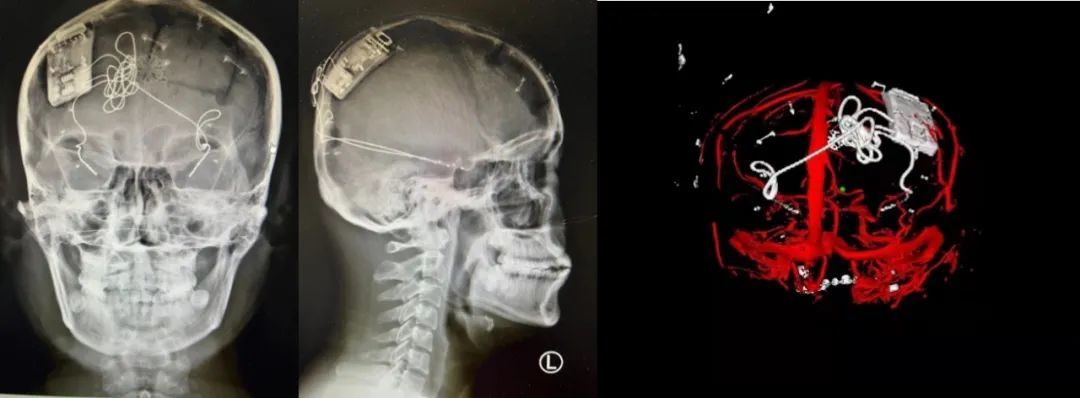

本次手術(shù)過程順利,術(shù)中刺激器各項指標(biāo)均工作正常,術(shù)后重建顯示電極位置精準(zhǔn),腦電信號清晰?;颊邽槟行?,入院后診斷為雙側(cè)顳葉癲癇,此類癲癇為開顱手術(shù)的相對禁忌癥,在藥物無法控制的情況下,傳統(tǒng)治療效果欠佳 。

術(shù)前經(jīng)過宣武醫(yī)院癲癇多學(xué)科專家團隊詳細(xì)的臨床評估,包括視頻腦電監(jiān)測、頭顱磁共振及三維 CT 掃描、腦核醫(yī)學(xué)檢查等,全面評估了患者病情及致癇灶定位情況。

由于患者臨床診斷為雙側(cè)顳葉癲癇伴海馬硬化,無法通過致癇灶切除等傳統(tǒng)外科手術(shù)方式獲益,決定進行閉環(huán)反應(yīng)性神經(jīng)刺激系統(tǒng)植入手術(shù)治療。并根據(jù)閉環(huán)神經(jīng)刺激技術(shù)特點,為患者“量身定制”植入方案,尤其是電極植入位點和脈沖發(fā)生器固定部位等,為手術(shù)的順利實施奠定了良好基礎(chǔ)。

團隊根據(jù)術(shù)前計劃,在手術(shù)機器人輔助下完成雙海馬長軸電極及 IPG 植入,術(shù)后重建顯示電極位置精準(zhǔn),腦電信號清晰。術(shù)后第二天,患者即下床活動,身體狀況恢復(fù)良好。